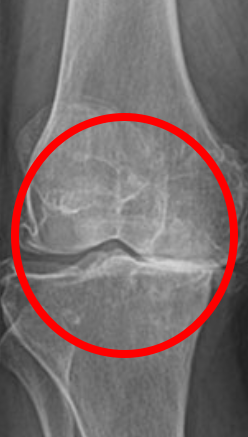

"관절 통증 때문에 일상생활이 불편해요. 어떤 관절 건강 기능식품을 먹어야 할까요?" 많은 분들...

관절영양제 통증이 있다면 호관원으로

안녕하세요! 정직한 건강식품 문화를 선도하는 기업 '자연내림' 입니다. 삶의 질을 결정짓는 것...

무릎 영양제 추천 핵심성분 확인하고 호관원 콘드로이친 선택

무릎 영양제 추천 핵심성분 확인하고 호관원 콘드로이친 선택 글루코사민은 정말 유명한 원료이기 때문에 ...